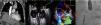

A. TC de tórax con contraste: compresión de la aurícula derecha por la elevación del hemidiafragma ipsilateral (flecha azul). B y C. Ecocardiograma transesofágico: cortocircuito derecha-izquierda a través del foramen oval (paso de contraste a la aurícula izquierda –flecha amarilla–, doppler color –flecha blanca–). D. Implante de dispositivo Amplatzer® (flecha roja).

AD: aurícula derecha; AI: aurícula izquierda; Ao: aorta ascendente; VCI: vena cava inferior.

No existían datos de insuficiencia cardiaca o infección respiratoria, y la parálisis diafragmática derecha se confirmó mediante ecografía diafragmática. La analítica básica era normal y se realizó una TC de tórax con contraste que descartó la presencia de tromboembolismo pulmonar o afectación parenquimatosa, y puso de manifiesto una importante compresión de la aurícula derecha (AD) y atelectasia parcial del lóbulo inferior del pulmón derecho por el hemidiafragma ipsilateral (fig. 1A). Las pruebas de función respiratoria mostraron un trastorno mixto leve-moderado (CVF 76%, FEV1 64%, FEV1/CVF 65%), sin alteración de la difusión de monóxido de carbono.

La ausencia de neumopatía que explicara la hipoxemia grave, así como la pobre respuesta a oxigenoterapia hicieron sospechar la existencia de un cortocircuito derecha-izquierda intracardiaco o intrapulmonar. En el ecocardiograma transtorácico se informó de un probable foramen oval permeable (FOP) por paso inmediato de burbujas a cavidades izquierdas a través del septo interauricular tras la administración intravenosa de suero salino agitado. Las cámaras cardiacas no estaban dilatadas y las presiones pulmonares eran normales. Se realizó un estudio transesofágico que mostró una AD severamente reducida por compresión extrínseca y confirmó la presencia de un cortocircuito derecha-izquierda a través de un FOP (fig. 1B y C).

Ante la presencia de insuficiencia respiratoria y síntomas compatibles con síndrome de platipnea-ortodeoxia se indicó el cierre percutáneo del FOP. Se implantó un dispositivo de foramen oval Amplatzer® n.o 18 (St Jude Medical, EE. UU.) con guía de ecografía transesofágica (fig. 1D), persistiendo un mínimo cortocircuito residual. Tras el procedimiento el paciente presentó una importante mejoría clínica y gasométrica, y mantenía al alta una SpO2 estable superior al 94% respirando aire ambiente.